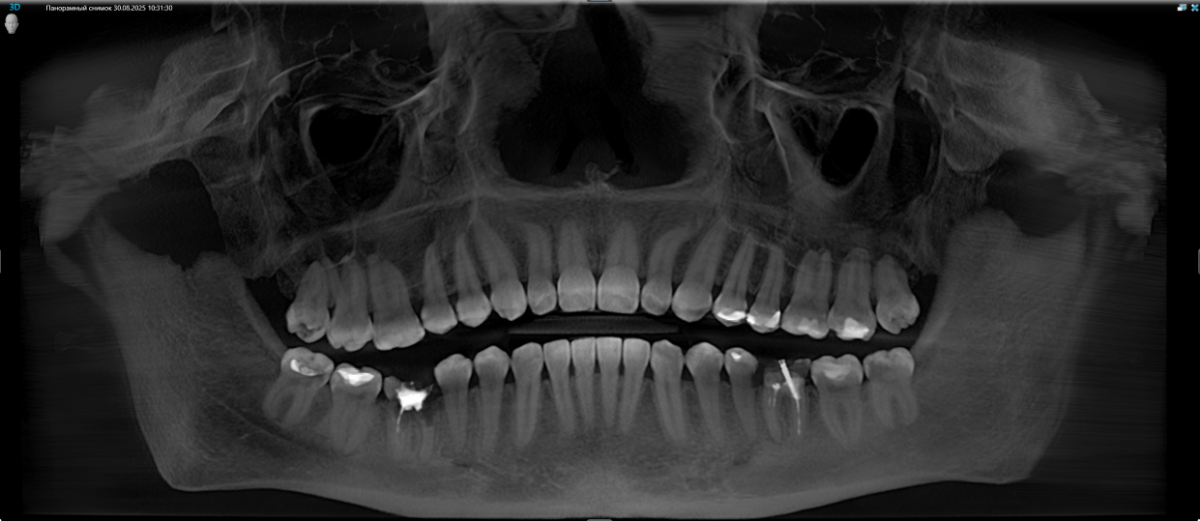

Здравствуйте, подскажите, целесообразно и нужно ли в моем случае ортодонтическое лечение? После лечения зубов планирую установку имплантов в области 36 и 46 зубов. Нужно ли что-то исправлять, или в моем случае можно поставить импланты как есть, без негативных последствий со стороны прикуса? Ортопед на консультации сказал, что можно, по поводу прикуса ничего сказано не было. Была у 2 ортодонтов: первый сказал, что прикус глубокий, и нужно исправлять брекетами. Второй сказал, что небольшие нарушения есть, но как я поняла, не сильно критичные (в области верхних резцов, боковых зубов на верхней челюсти, поэтому наблюдается оголение десны из того, что запомнила), и рекомендовал лечение элайнерами. Жалоб нет, кроме бруксизма (врачи сказали, что причина не в прикусе) и смущает выдвинувшийся 16 зуб. Этот панорамный снимок выдали после КТ, КТ также есть на диске. Спасибо.

Панорама.png